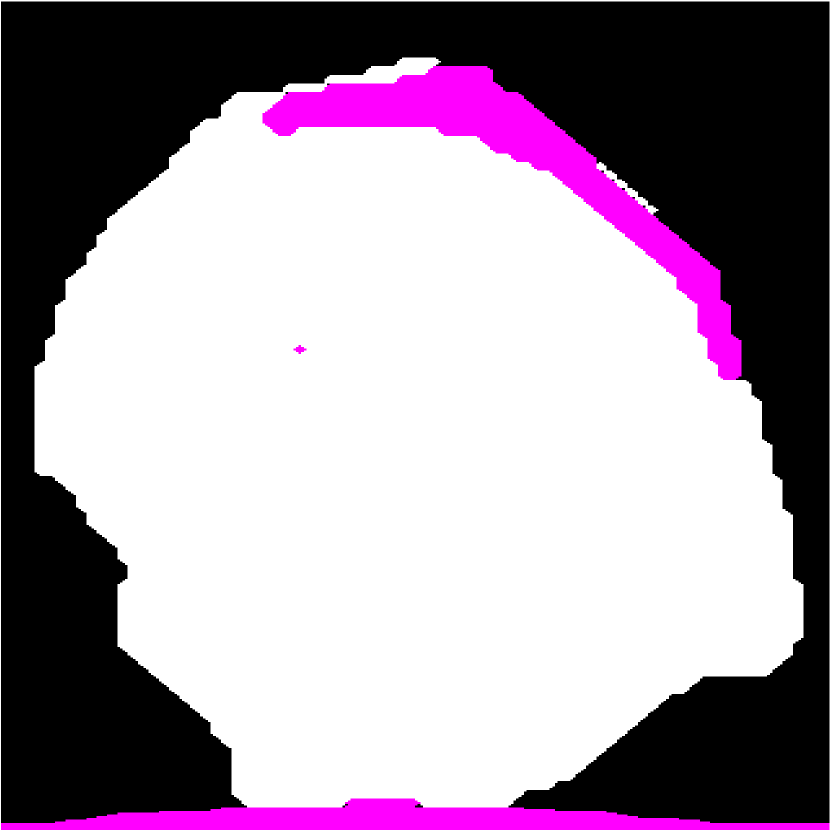

Figure 1(a) shows a representative HFU image of a human LN immersed in a phosphate-buffered saline (PBS) bath. Two different LN tissue types are visible: LNP (inside) and fat (surrounding). In order to perform QUS processing successfully, a 3D segmentation method is required to restrict QUS processing to LNP and to correct accurately for ultrasound attenuation [2]. Furthermore, accurate segmentation can provide detailed LNP shape information, which can be used to produce additional bio-markers of cancer.

Automatic LN segmentation in HFU images faces several challenges, such as speckle noise, low contrast between LNP and fat, implicit boundary and spatially varying intensity distributions caused by acoustic attenuation and focusing effects. Therefore, obtaining satisfactory results with intensity information alone is not possible. To illustrate this point, Figure 1(c) shows the result of a K-means analysis, which clusters voxels based on their intensities. Compared to manual segmentation result, some LNP voxels with high intensity are mislabeled as fat, and some LNP voxels with low intensity are mislabeled as PBS. Due to speckle noise and spatially varying intensity distributions in HFU images, other intensity-based segmentation methods such as region growing [7] would also yield unsatisfactory results.

Figure 1: (a) Target HFU image. (b) Manual-segmentation result by an expert. LNP is white and fat region is pink. The vertical axis is depth. (c) The segmentation result obtained by K-means.